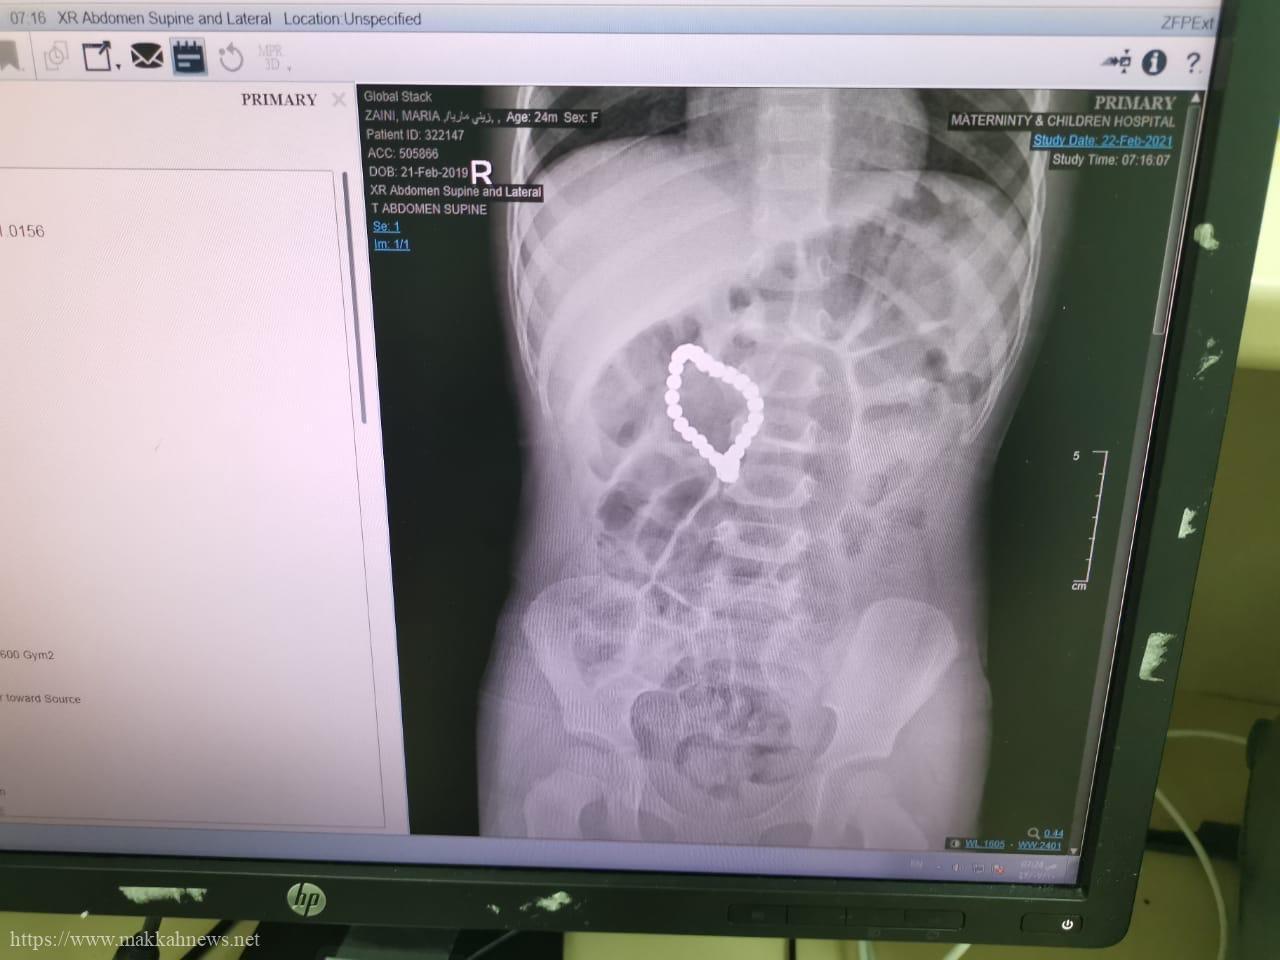

فريق طبي بولادة مكة ينجح في إنقاذ طفلة إبتعلت كرات مغناطسية

مكة المكرمة – تمكن فريق طبي في مستشفى الولادة والأطفال بمكة عضو تجمع مكة المكرمة الصحي من إنقاذ حياة طفلة تبلغ…